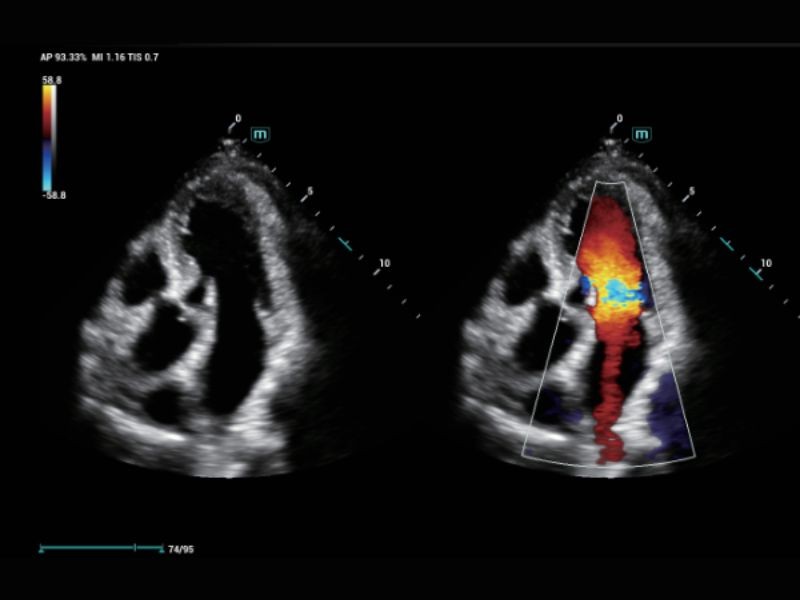

Avaliação da sincronização miocárdica com análise quantitativa

AutoEF

Medição automática da fração de ejeção por quadros de diástole/sístole

RIMT

Medição IMT em tempo real baseada em dados de RF

R-VQS

Coeficiente de dureza vascular e velocidade da onda de pulso (PWV)